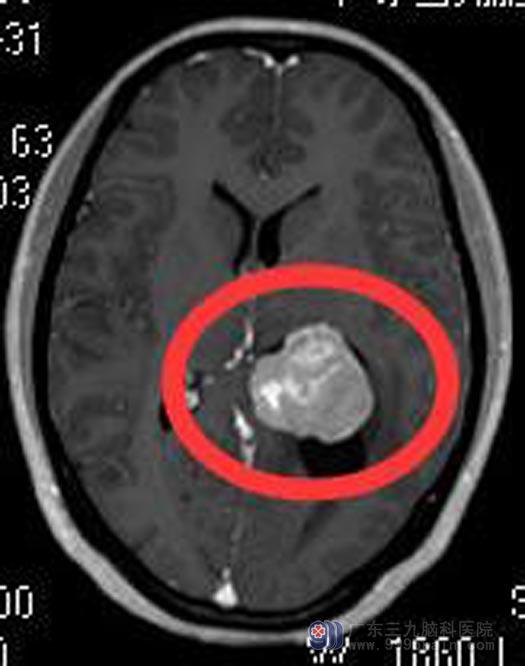

家里人立即火急火燎地赶到广东三九脑科医院综合神经外科,进一步头颅MR检查提示:左侧侧脑室后角内占位性病变,大小约3.6cm×3.4cm×3.3cm,考虑脑膜瘤可能。

完善术前检查后,鲁明主任主刀,在全麻下行左侧脑室后角占位切除术,术中显微镜下见灰白色肿瘤组织,肿瘤质脆,血供丰富,边界清晰;镜下用激光刀分块全切除肿瘤,手术经过顺利。术后,阿香头痛症状好转,康复出院。病理回报:脑膜瘤,纤维细胞型,WHO I级。